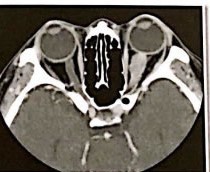

fistula carotido cavernosa